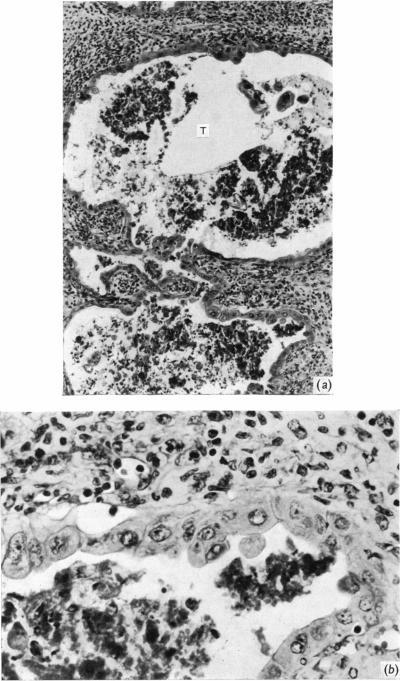

As a contribution to the problem of the immunological privilege of the fetus it was decided to investigate the fate of yolk sac grafts in mice. Ten-day post-coitum mouse visceral yolk sac was transplanted to a dermal tunnel in the flank of isogeneic animals. In this site the yolk sac was capable of surviving for at least 15 days past the normal duration of pregnancy. Yolk sac was transplanted to a similar site in allogeneic animals and was found to be destroyed by an immunological reaction within 13 days. Orthotopic skin grafts between the same strains of mice used in the yolk sac transplantation were rejected in first-set fashion within 13 days. A limited series of host animals, previously sensitized by visceral yolk sac, rejected orthotopic skin grafts in second-set fashion. These findings indicate that the cells of the visceral yolk sac in the mouse contain transplantation antigens. Possible reasons why such antigens do not lead to fetal rejection during pregnancy are considered.

为了研究胎儿免疫特权问题,决定对小鼠卵黄囊移植的命运进行研究。将受孕10天的小鼠内脏卵黄囊移植到同基因动物胁腹的皮肤隧道中。在此部位,卵黄囊能够在超过正常孕期的时间内存活至少15天。将卵黄囊移植到异基因动物的类似部位,发现其在13天内被免疫反应破坏。在卵黄囊移植中使用的相同品系小鼠之间的原位皮肤移植在13天内以初次排斥的方式被排斥。一系列有限的先前经内脏卵黄囊致敏的宿主动物以二次排斥的方式排斥原位皮肤移植。这些发现表明,小鼠内脏卵黄囊的细胞含有移植抗原。文中还考虑了此类抗原在孕期为何不会导致胎儿被排斥的可能原因。